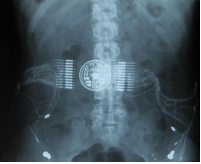

The motivation approach is the complementary research works of

these teams. Indeed, a collaborative project should give an additional value to

their research results. On one hand, the DEMAR Project Team has experience in Functional Electrical Stimulation to restore or modulate

movements on spinal cord injured patients and post stroke patients. In both pathologies researches on assisted gait using

FES (for paraplegics with a

walker and hemiplegics) are

carried out in the team (cf. Figure 1).

Figure 1: (a) Paraplegic patient walking under FES, (b) Implanted

FES stimulator